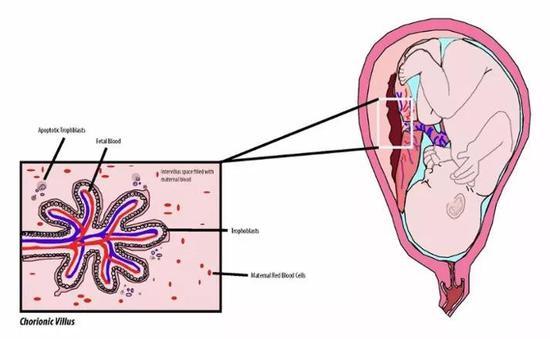

而目前使用最广泛的检测方法是穿刺羊水检查。

在孕期的14周左右,用长针筒穿刺母亲腹部抽取羊水。

在高倍镜下观察羊水中细胞染色体的数量和形态。

它直接对染色体进行分析,具有99%的检出率。

但这种侵入性检测方法因有0.16%的流产概率而让人心存顾虑。